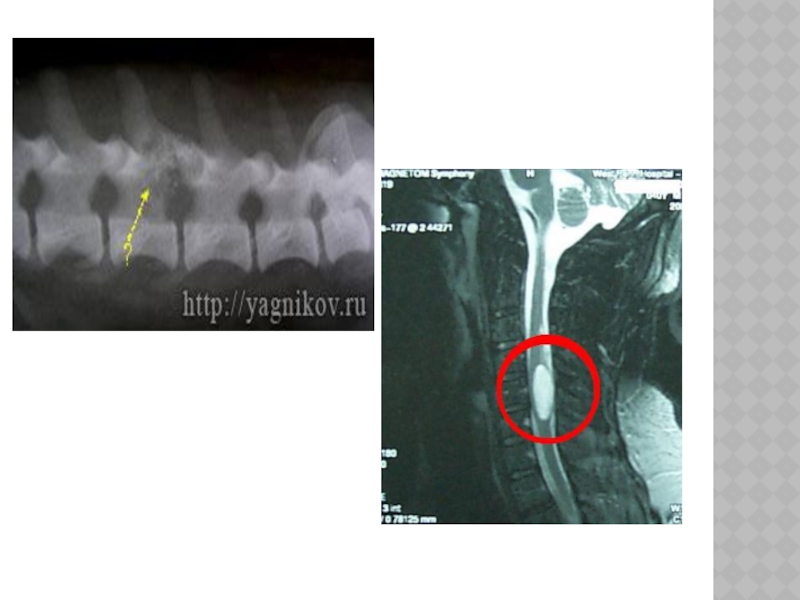

Слайд 123ОПУХОЛИ СПИННОГО МОЗГА

Классификация:

-интрамедуллярные(развивающиеся из вещества спинного мозга и

располагающиеся внутри нег - экстрамедуллярные( образующиеся из мозговых оболочек, корешков и локализующиеся вне спинного мозга).

Слайд 124КЛИНИКА

Экстрамедуллярные опухоли- развиваются развитии в три стадии : корешковые расстройства, частичного

и полного сдавливания спинного мозга.

-корешковая стадия- корешковые боли(радикулит) -стадия частичного сдавливания спинного мозга синдром Броуна - Секара: спастический парез конечности (конечностей),расстройство глубокой чувствительности на стороне поражения, расстройство поверхностной чувствительности на противоположной стороне.

- стадия полного сдавливания спинного мозга- двухсторонний парез/ паралич, расстройства чувствительности, тазовые нарушения.

Слайд 125

Интрамедуллярные опухоли- обнаруживаются неврологическими нарушениями в месте своего роста:

- в

шейном отделе-вялый парез рук, снижение поверхностной чувствительности на руках, признаки сдавливания спинного мозга - центральные парезы ног, расстройства чувствительности по проводниковому типу, боли, оболочечные симптомы.

Слайд 126ДИАГНОСТИКА.

Клиника, люмбальная пункция, миелография, КТ, МРТ.

Слайд 127ЛЕЧЕНИЕ

1.Оперативное. 2. Симптоматическая терапия(уменьшение болей, отека спинного мозга).